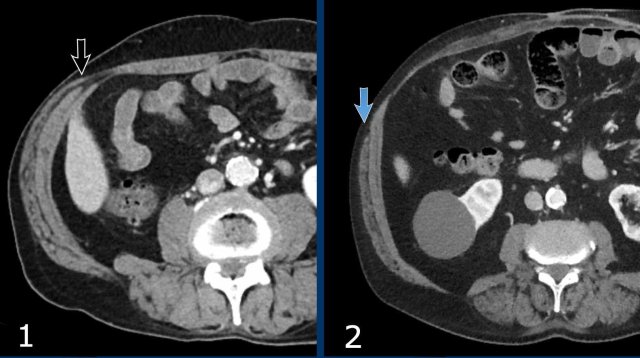

These images are of a 78 year old morbid obese female who has an incisional midline hernia.

Study the images and then compare to the next images, who were taken one month later, when she presented with a painfully swolen hernia.

Now there are signs of strangulation namely:

• New small bowel feces sign, best see on the transverse images (white arrow).

• Infiltration of mesenteric fat (black arrow).